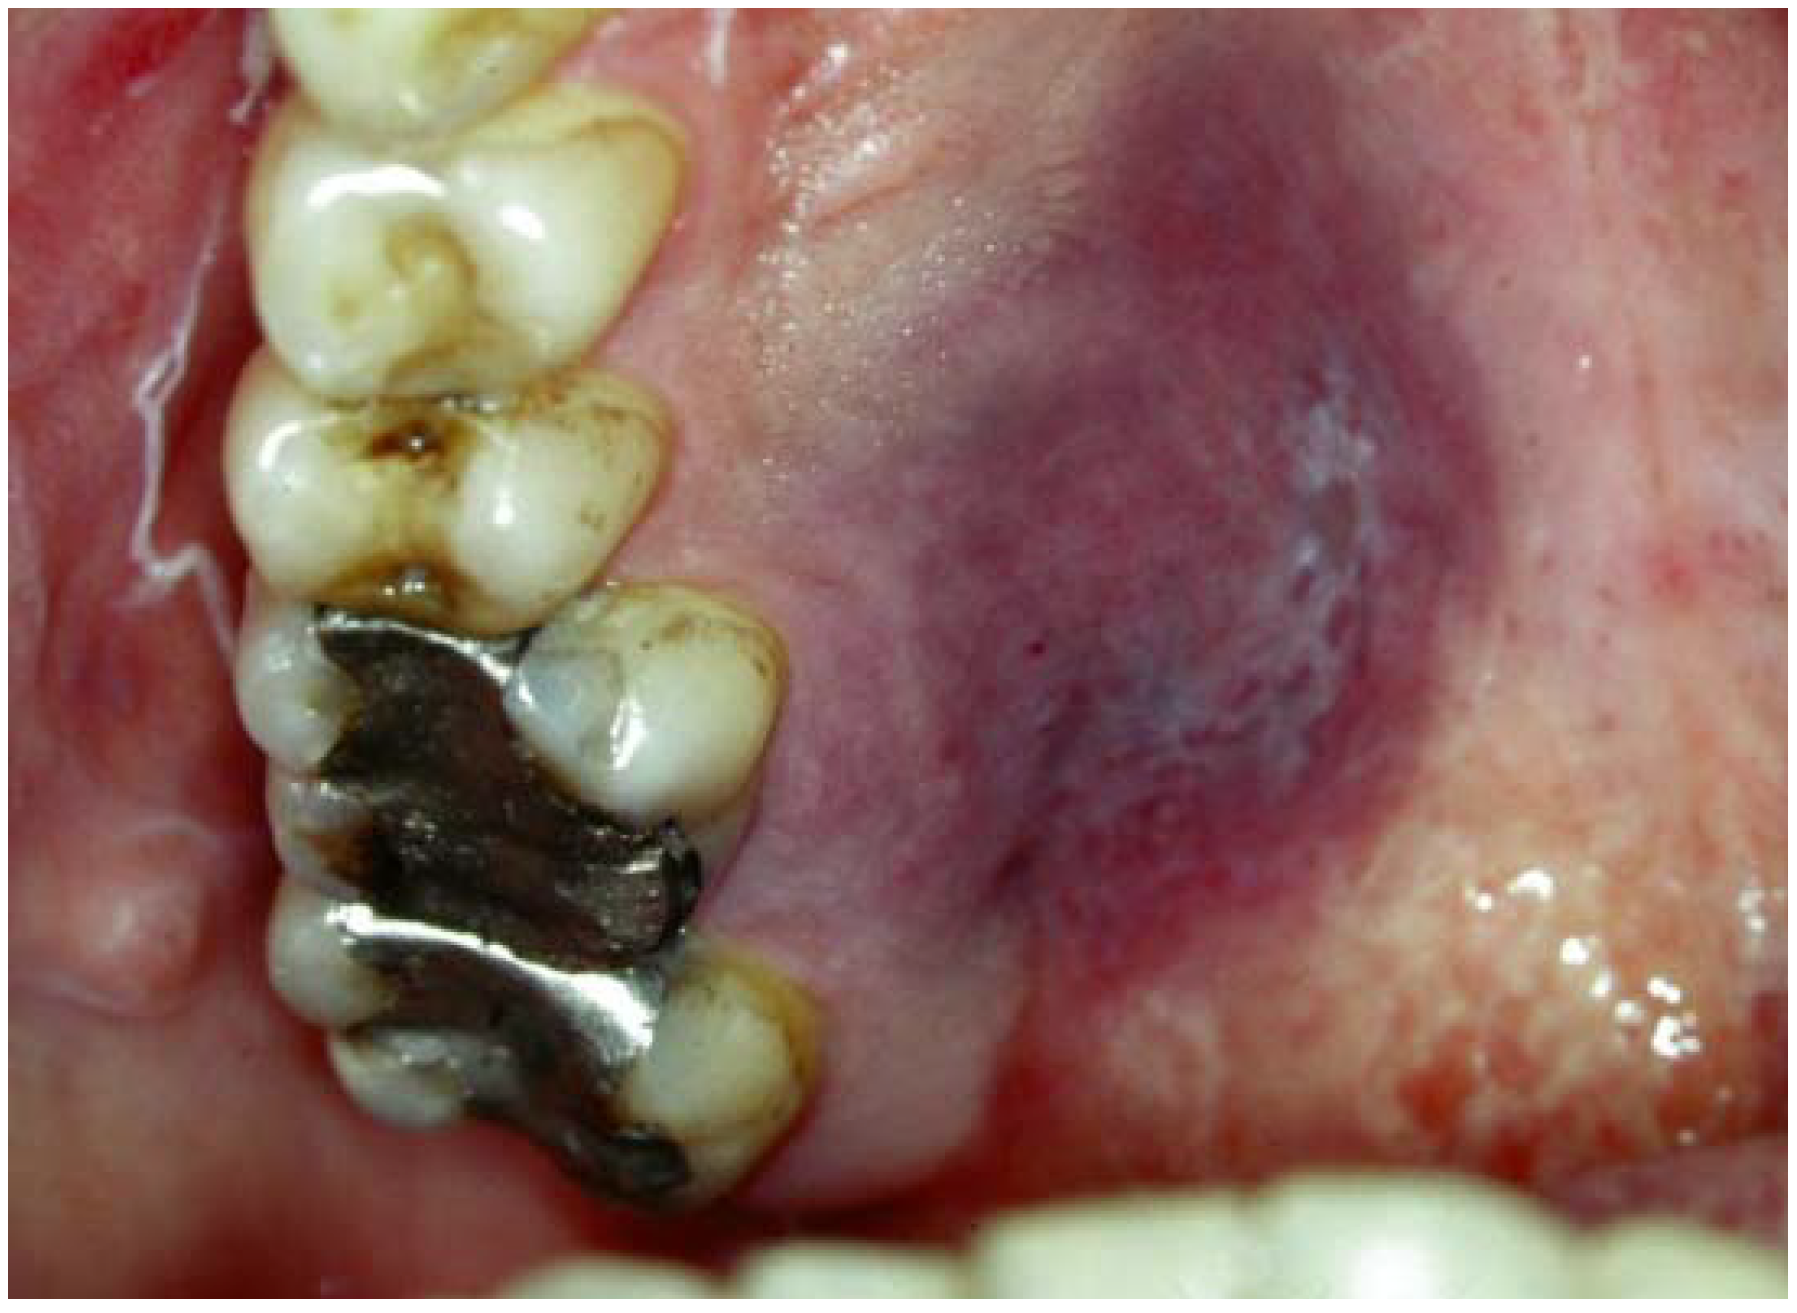

AIDS/HIV Associated Lesions and Management IntechOpen

AIDS/HIV Associated Lesions and Management IntechOpen What Are Hiv Lesions Learn how to recognize and treat different. An hiv rash is irritated skin that affects people who have the virus. Learn about the common skin problems that people with hiv or aids may have, such as syphilis, molluscum contagiosum, kaposi sarcoma, and more. Find out how to recognize, prevent, and treat these skin conditions with antiretroviral. Learn about the common. What Are Hiv Lesions.

AIDS/HIV Associated Lesions and Management IntechOpen What Are Hiv Lesions Find out how to recognize, prevent, and treat these skin conditions with antiretroviral. Learn about the common skin problems that people with hiv or aids may have, such as syphilis, molluscum contagiosum, kaposi sarcoma, and more. Learn how to recognize and treat these conditions, and how they relate to. Learn how to recognize and treat different. Learn about the types. What Are Hiv Lesions.

AIDS/HIV Associated Lesions and Management IntechOpen What Are Hiv Lesions Hiv can cause various skin lesions, such as herpes, oral hairy leukoplakia, and molluscum contagiosum. Learn how to recognize and treat different. Learn what an hiv rash looks like, how it can be an early sign of infection, and how to treat it. Find out how to recognize, treat,. An hiv rash is irritated skin that affects people who have. What Are Hiv Lesions.